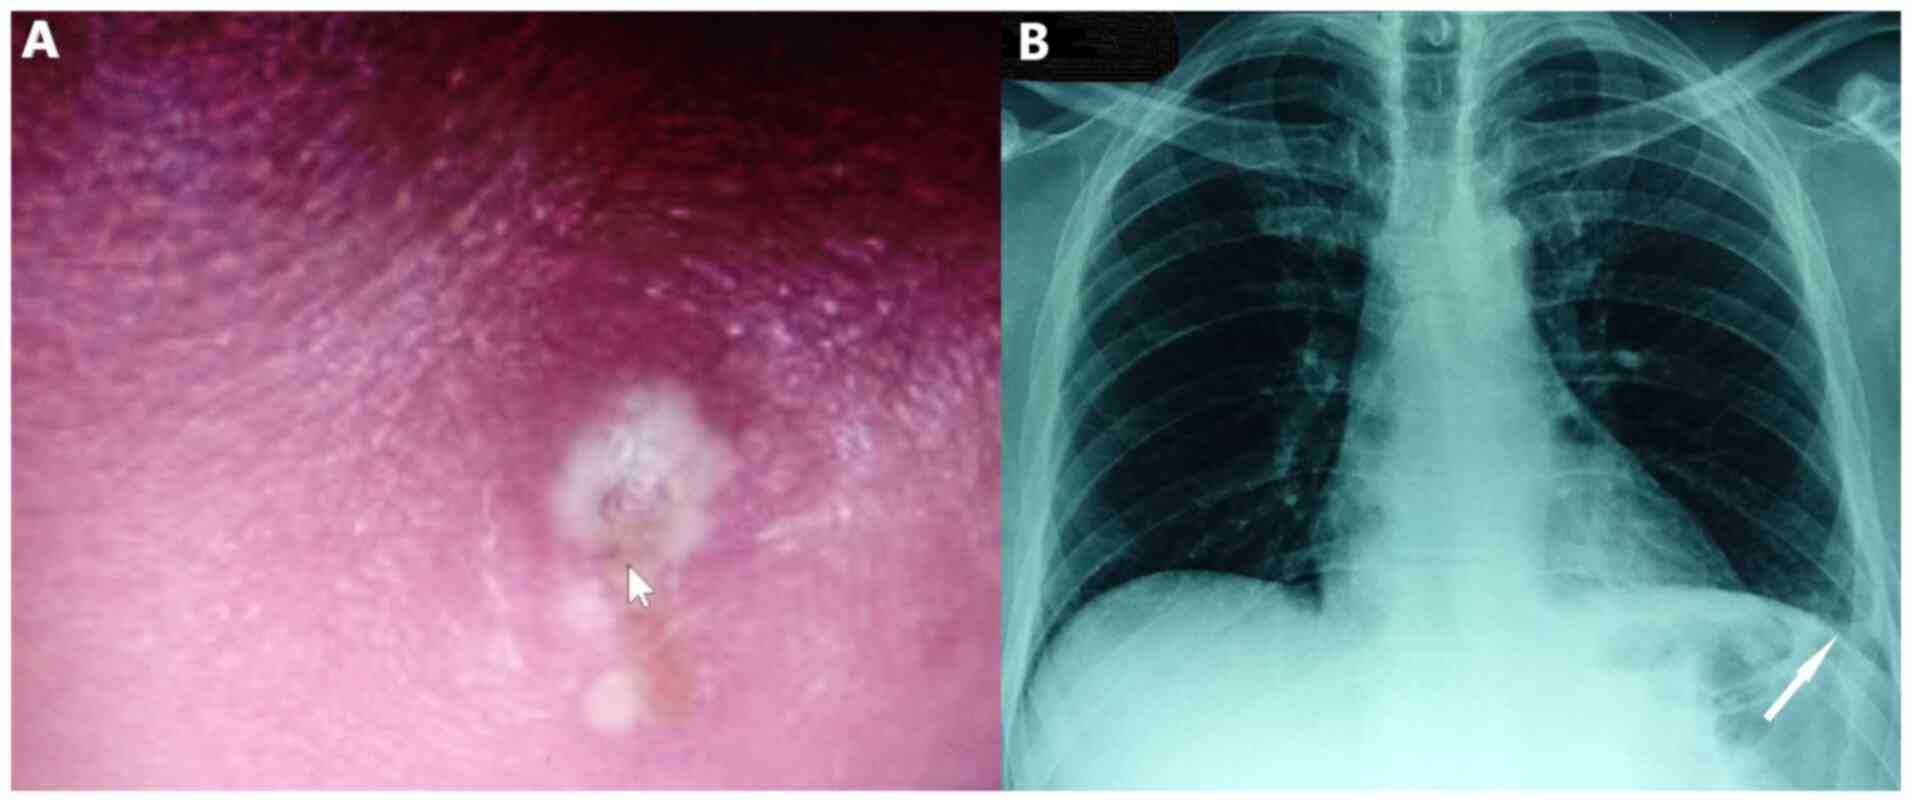

Clinical evaluation revealed a febrile patient with dullness on percussion and crackles on auscultation at the base of the left lung. He also had boils and carbuncles in his face, with a pus-filled, 1 cm in greatest dimension, skin lesion on his forehead. The skin over the infected area was red and swollen (Fig. 1A). Physical examination of the oropharyngeal region did not reveal abnormal findings. Clinical examination did not also reveal neck lymph node enlargement or obvious inflammation of neck skin and soft tissues.

Figure 1

The skin lesion and chest X-ray on admission. (A) Pus-filled, 1 cm in greatest dimension, skin lesion on the patient’s forehead. The skin over the infected area is red and swollen. (B) Chest X-ray shows consolidation in the left lower lobe with blunting of the left costophrenic angle.

Blood pressure was 150/85 mmHg, heart rate was 89 beats per minute, oxygen saturation was 96% on room air and body temperature was 38.6˚C. Electrocardiography did not reveal abnormal findings on admission. Chest X-ray revealed consolidation in the left lower lobe with blunting of the left costophrenic angle (Fig. 1B).